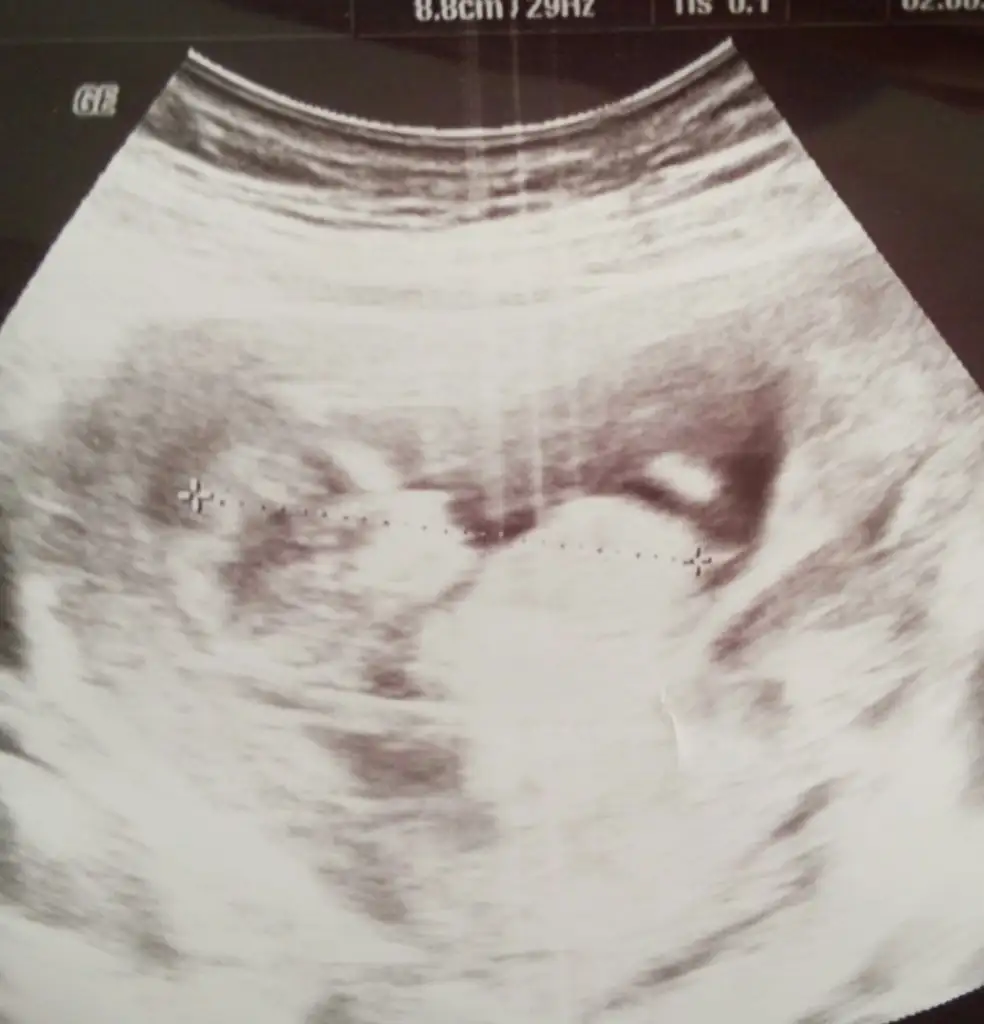

Canım sen daha iyi anlıyosun bu nub olayından benimkine de bi baksanda tahminde bulunsann lütfennnnn :)

Merhaba kızlar ben de uzun zamandır sizleri takip ediyorum dayanamadım üye oldum sonunda. :) Bu da bizim dünkü ultrason görüntümüz burada 12+4 günlük sizce cinsiyeti nedir?